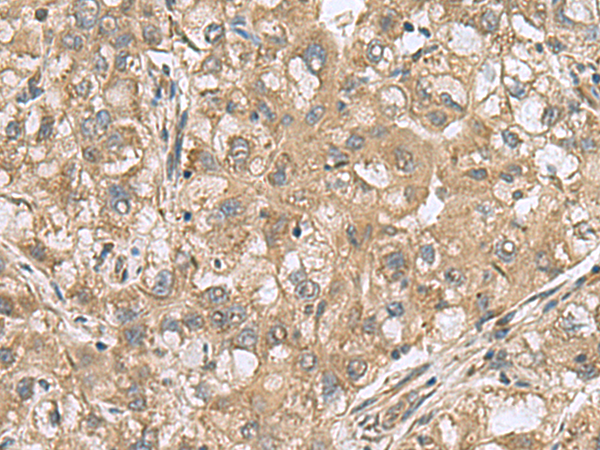

IHC positive control:

Human liver cancer and Human cervical cancer

IHC Recommend dilution:

50-300